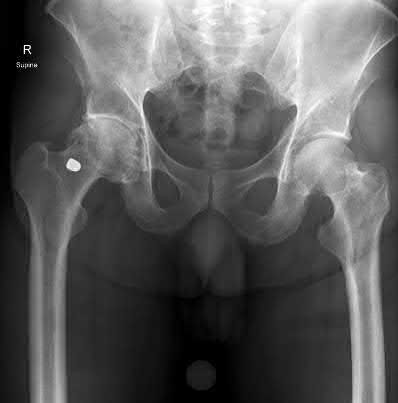

A 76-year-old male community ambulatory presented to clinic complaining of pain in the left groin that has been persistent for the last 8 months. Radiographs obtained from clinic are seen in Figure A. You suspect a femoral neck nonunion and obtain a CT scan which confirmed it. Which of the following statements is true?

A total hip arthroplasty (THA) after nonunion of a femoral neck fracture would provide the best long term outcomes in a 76-year-old male who is a community ambulator.

After nonunion of a femoral neck fracture, hemiarthroplasty and THA are good salvage option for the physiologically older patients. When deciding between these two options, THA is better for active and cognitively intact patients. THA is also indicated in patients with radiographic evidence of degenerative disease about the acetabulum. Hemiarthroplasty is advocated for patients who are older and less active.

Yang et al. retrospectively investigated the risk factors for nonunion in patients treated with cannulated screws. They reviewed 202 patients who had femoral neck fractures and were treated with internal fixation with cannulated screws. They identified that triangle configuration, displaced fracture, borderline or unacceptable reduction, and increased screw shaft subchondral purchase over the femoral neck were all risk factors for nonunion after internal fixation.

Inverted triangle configuration was found to increase rate of union.

Archibeck et al. retrospectively reviewed the outcomes of 102 THAs after failed internal fixation for a hip fracture (including both femoral neck and intertrochanteric). They concluded that the conversion of failed hip internal fixation has elevated risks compared to a primary THA, however, it may still be successful. The biggest concern for these patients postoperatively are periprosthetic fracture and dislocation.

Figures and Illustrations:

Figure A is an AP pelvic radiograph demonstrating a nonunion of a femoral neck fracture after suboptimal fixation with 3 cannulated screws in a triangle configuration.

Illustration A is an AP radiograph of the left hip in this patient following conversion to THA.